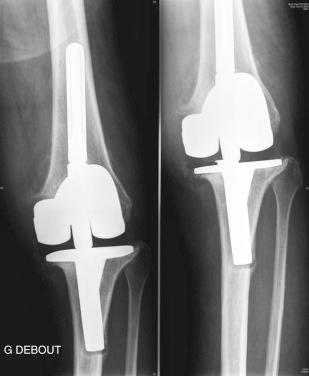

We performed a one-stage exchange with reconstruction using a stabilized prosthesis with cemented stem extensions. Intraoperative samples confirmed the diagnosis of infection, and culture grew Propionibacterium acnes . Postoperative antibiotic treatment was given intravenously for 2 weeks and orally for 3 months. The postoperative course was uneventful. At follow-up after 2 years, the patient had no complaints of knee pain. There were no signs of persistent infection, and no pathologic changes were observed on the final radiographs ( Fig. 35.4 ).

FIGURE 35.4, Case 2: Standard final radiographs. A, Anteroposterior view. B, Lateral view.